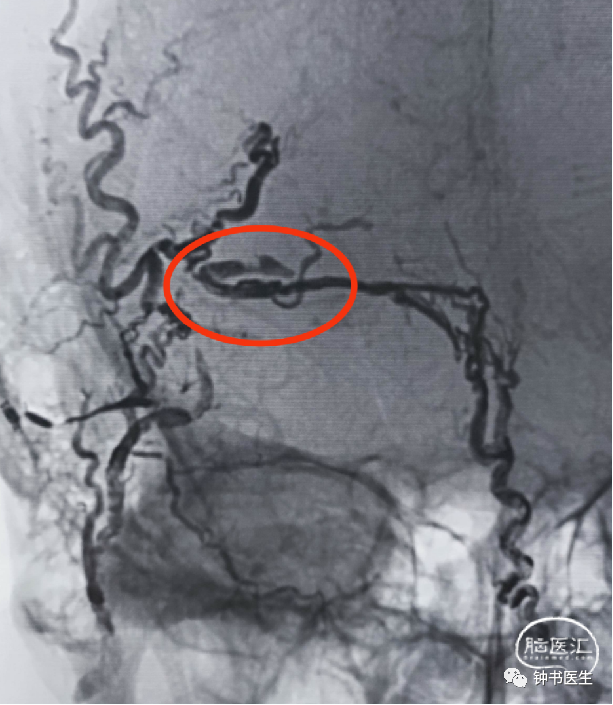

第二次栓塞

Apollo3cm超选脑膜中供血支,泰杰28+50%GB做塞子。

稀释为70%onyx18缓慢注射无法弥散到瘘口,考虑注射速度偏慢!

马拉松塑形超选脑膜后动脉供血支。

用外科胶方式注射onyx18(保持胶流动性),弥散到瘘口。

术后即刻DSA:动静脉瘘消失!

返流压力锅技术:核心是保留胶流动性,使用三通双注射器注射onyx18,控制好力量和速度。